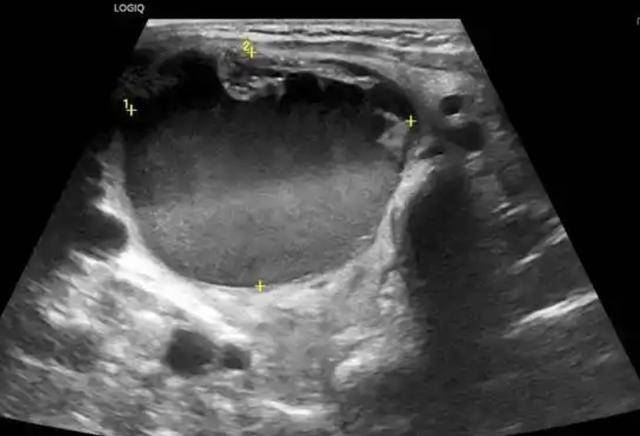

坚持少糖、少油炸、少腌制,远比一味“少盐少油”更关键。体检别只看“血糖血脂”,留意甲状腺。每年体检时,建议顺带查一下甲状腺彩超和甲状腺功能(如TSH、FT4等)。